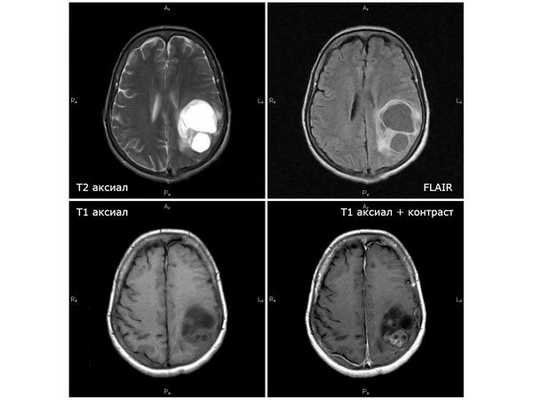

Магнитно-резонансная томография с использованием контрастного препарата является наиболее информативным методом диагностики злокачественных глиом. МР-картина глиобластомы достаточно специфична - это объемное образование с выраженным перифокальным отеком, участком (обычно) периферийного накопления контрастного препарата и центральной некротической зоной. В большинстве случаев диагноз глиобластомы по данным качественных МР-снимков не вызывает каких-либо сложностей, однако ряд патологий имеет схожие МР-характеристики, что требует проведения дифференциального диагноза - метастазы, абсцессы головного мозга и (наиболее сложно) первичная лимфома центральной нервной системы.

В день поступления пациентке выполнена МСКТ (мультиспиральная компьютерная томография) головного мозга без контрастного усиления: выявленные изменения расценены как два объёмных образования в левом полушарии мозга размерами 10*10 мм и 25*35 мм с умеренным отёком вокруг опухоли. МРТ головного мозга с контрастным усилением показало объёмное кистозно-солидное образование размерами 51*53*64 мм с умеренным отёком вокруг опухоли. Проведён онкопоиск: УЗИ органов брюшной полости, малого таза и молочных желез, МСКТ органов брюшной полости с контрастированием и ФГДС (гастроскопия). Первичный очаг не обнаружен.

Первая диагностическая МРТ от 11.08.18: кистозно-солидное объёмное образование с отёком вокруг опухоли